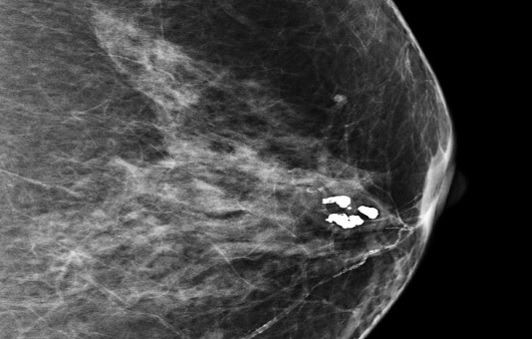

유방 미세석회화는 유방 조직 내에 칼슘 성분이 미세하게 침착된 현상을 말합니다. 이러한 석회화는 보통 크기가 매우 작아 육안으로는 확인이 불가능하며, 유방촬영술(mammography)을 통해서만 발견됩니다. 미세석회화는 대부분 증상이 없어 건강검진이나 유방촬영에서 우연히 발견되는 경우가 많습니다.

악성 미세석회화의 특징

악성 미세석회화는 다음과 같은 특징을 보입니다.

- 크기가 작고 미세함

- 불규칙한 모양과 크기

- 군집성(5개 이상이 한 곳에 모여 있는 형태)

- 선형 또는 분지형 배열

- 시간이 지남에 따라 수와 분포의 변화가 있음

이러한 특징을 가진 미세석회화는 유방암 또는 전암성 병변과 연관될 가능성이 높습니다. 특히 비침윤성 유관암(DCIS)이나 침윤성 유관암의 초기 단계에서 이러한 형태의 미세석회화가 자주 관찰됩니다. 따라서 이러한 소견이 보이면 추가 조직검사와 적절한 치료가 필요합니다.